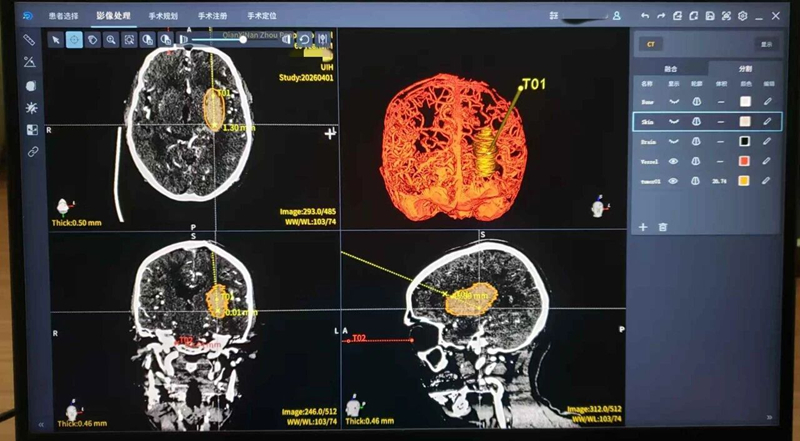

术前机器人3D重建,精准规划入路,避开血管

手术中,团队首先通过机器人系统完成患者头颅CT三维重建,精准规划穿刺路径,将误差控制在1毫米以内,有效避开了颅内重要血管与神经。在机器人精准引导下,可视化引流管直达血肿核心,医生可通过屏幕实时监测血肿清除过程,实现全程可视化操作,最终精准抽吸出约30ml积血。手术全程仅40分钟,切口仅2-3mm,创伤极小、术中出血少。术后复查CT显示,血肿基本完全清除,引流管位置精准无误。患者意识迅速恢复,右侧肢体肌力显著改善,无新发神经功能障碍,目前已进入康复阶段。

头架固定、机器人辅助下植入可视化系统进入血肿腔